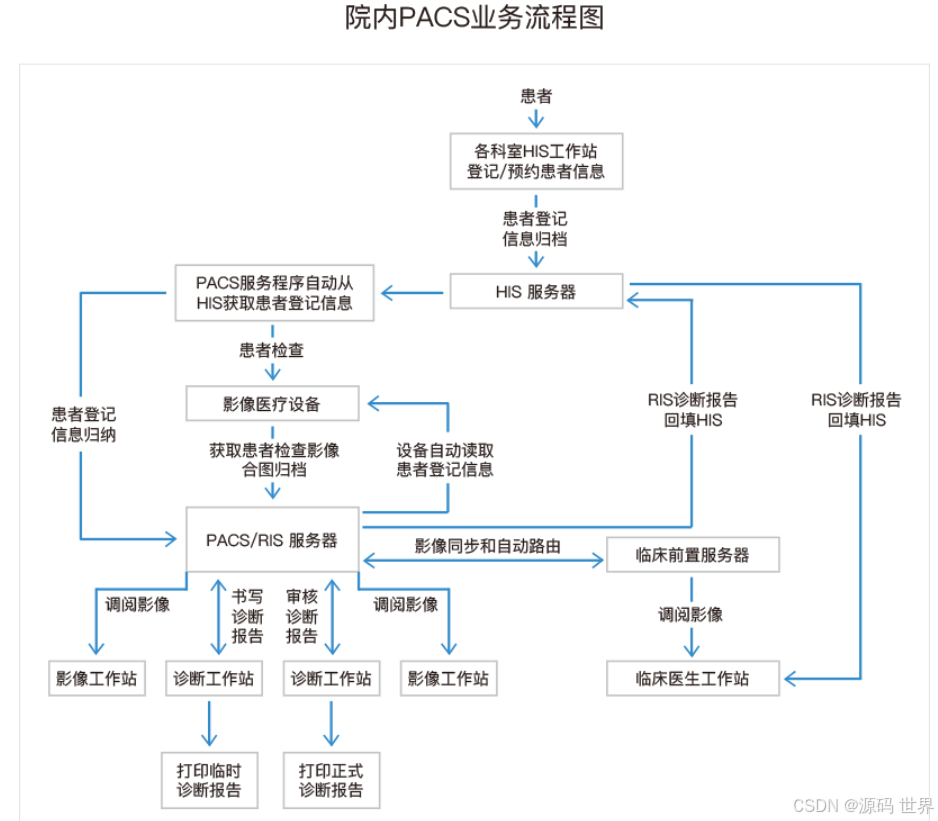

PACS系统业务流程

PACS流程从病人开始在HIS登记(挂号登记)或在RIS中进行检查登记开始。然后病人进入检查室,技师进行检查,接着阅片、书写报告和影像及图文报告归档。

1、临床医生在医生工作站中录入电子检查申请单,并将申请单传入RIS系统。

2、影像检查科室的RIS中对电子检查申请单的信息进行预约、审核、划价确认。

3、RIS与PACS的接口引擎通讯,向对方传递包括个人信息和检查信息的HL7消息。

4、PACS接口引擎通知归档服务器有新的需要调度的检查。

5、病人到达检查科室,检查设备向PACS接口引擎请求worklist。

6、对于支持worklist的DICOM设备,电子申请单直接传入影像设备,在影像设备中选择病人,直接安排检查。采集后的影像自动送往PACS;对于不支持worklist的影像设备,需要在设备中输入病人的基本信息。

7、技师进行检查操作,将得到的DICOM影像发送到采集工作站,在采集工作站完成质量控制等操作。

8、影像采集工作站接收到影像后,将影像送往PACS存储服务器。如果申请科室存在缓存服务器,则影像也同时发送到科室缓存服务器。

9、影像诊断医生根据需要调阅检查影像。

10、影像诊断医生对影像进行了修改或标注,则通知归档服务器更新信息并上传更新后的影像。

11、影像诊断医生在PACS诊断工作站上书写检查报告。

12、PACS接口引擎向HIS/RIS发送信息,通知更新检查状态。

13、临床医生获取影像和检查报告作为诊断的依据之一。

以上所描述的是现今常规的影像检查流程。随着数字影像设备和信息技术的快速发展,以及临床诊疗需求的变化,影像检查系统中的部分环节时有改变。不同医院的不同影像学检查也会不同。如急诊病人,影像科室会快速的先出一份急诊报告给医生进行紧急处理,最终正式的检查报告依据规范流程在之后送达临床科室。